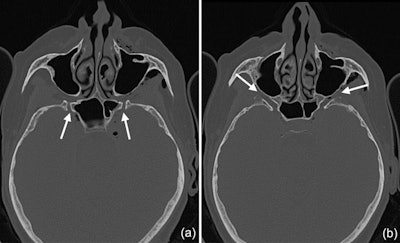

The woman's CT scans showed a deep peri-implant bone defect at the mesial aspect of implant #27 that extended almost into the sinus space, as well as a bone defect at the sinus wall, which was likely a remnant from the woman's prior sinus floor elevation procedure.

CT scans show that the pterygoid canal (a) and the forum rotundum (b) may be possible entry pathways for the air to enter the intracranial space. This is especially possible within the canal leading to the foramen rotundum, where several smaller air bubbles were captured.

"Hence, as the nozzle was inserted at the mesial aspect of the implant, the compressed air could have extended along the peri-implant defect into the augmentation material and then exited via this residual bone defect in the lateral sinual wall and into the surrounding soft tissue of the facial aspect of the posterior left maxilla," the authors wrote.